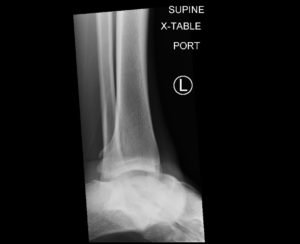

Subtalar dislocation is an unusual form of joint injury from high-energy trauma or athletic injuries. This case report describes a 22-year-old male who presented to the emergency department with left ankle pain after falling from his bicycle. Examination revealed significant deformity of the left foot and ankle. The foot pointed medially, and the bottom portions of the tibia and fibula were visible with the overlying skin intact. Radiographs confirmed left medial subtalar dislocation. There was no neurovascular compromise of the foot. The dislocation was successfully reduced under procedural sedation and the patient’s left leg was placed in a splint. He underwent post-reduction imaging and was instructed to remain non-weight-bearing and to follow up with orthopedics to discuss further management. The purpose of this report is to describe a case of a closed, medial subtalar dislocation and the approach to management.